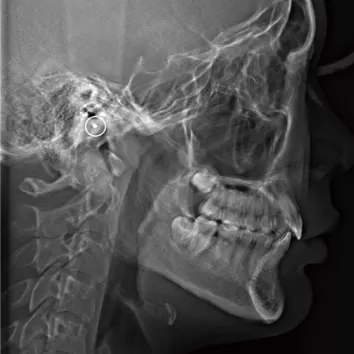

X-rays before treatment

[Panoramic Radiography/Lateral Cephalogram]